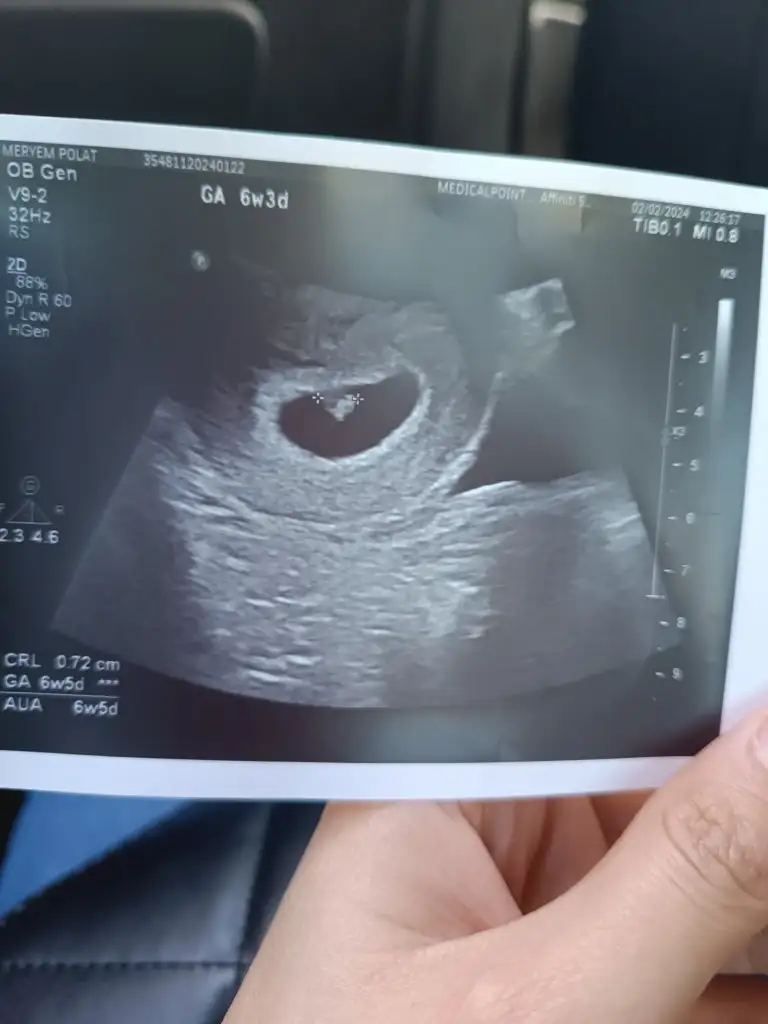

Bende kilo verdim hiçbir şey yiyip içemedim. Yani bebeğe yetecek kadar yedim ve gerçekten de öyle oldu bebeğin gelişimi bir hafta ilerde. Ama ben o kadar aç kalmışım ki vücut direncim çok düşmüş ve idrarda hem şeker hemde keton çıktı. Bu da açlıktan ve susuzluktan olmuş. Şimdi çok zorlanarak yiyorum ve tatlı yediğim zaman sabahlara kadar yatamıyorum çok rahatsızlanıyorum. Lütfen siz zorla da olsa yiyin. Kussanız da yiyin sağlıklı şeyler yiyin hep. İnanın bu zor günler geçicek. Benim şu an hastaneye yatıp sıvı almam lazım. Çünkü bebeğe geçerse büyük problem olur. Lütfen siz dikkat edin sizde de olmasın